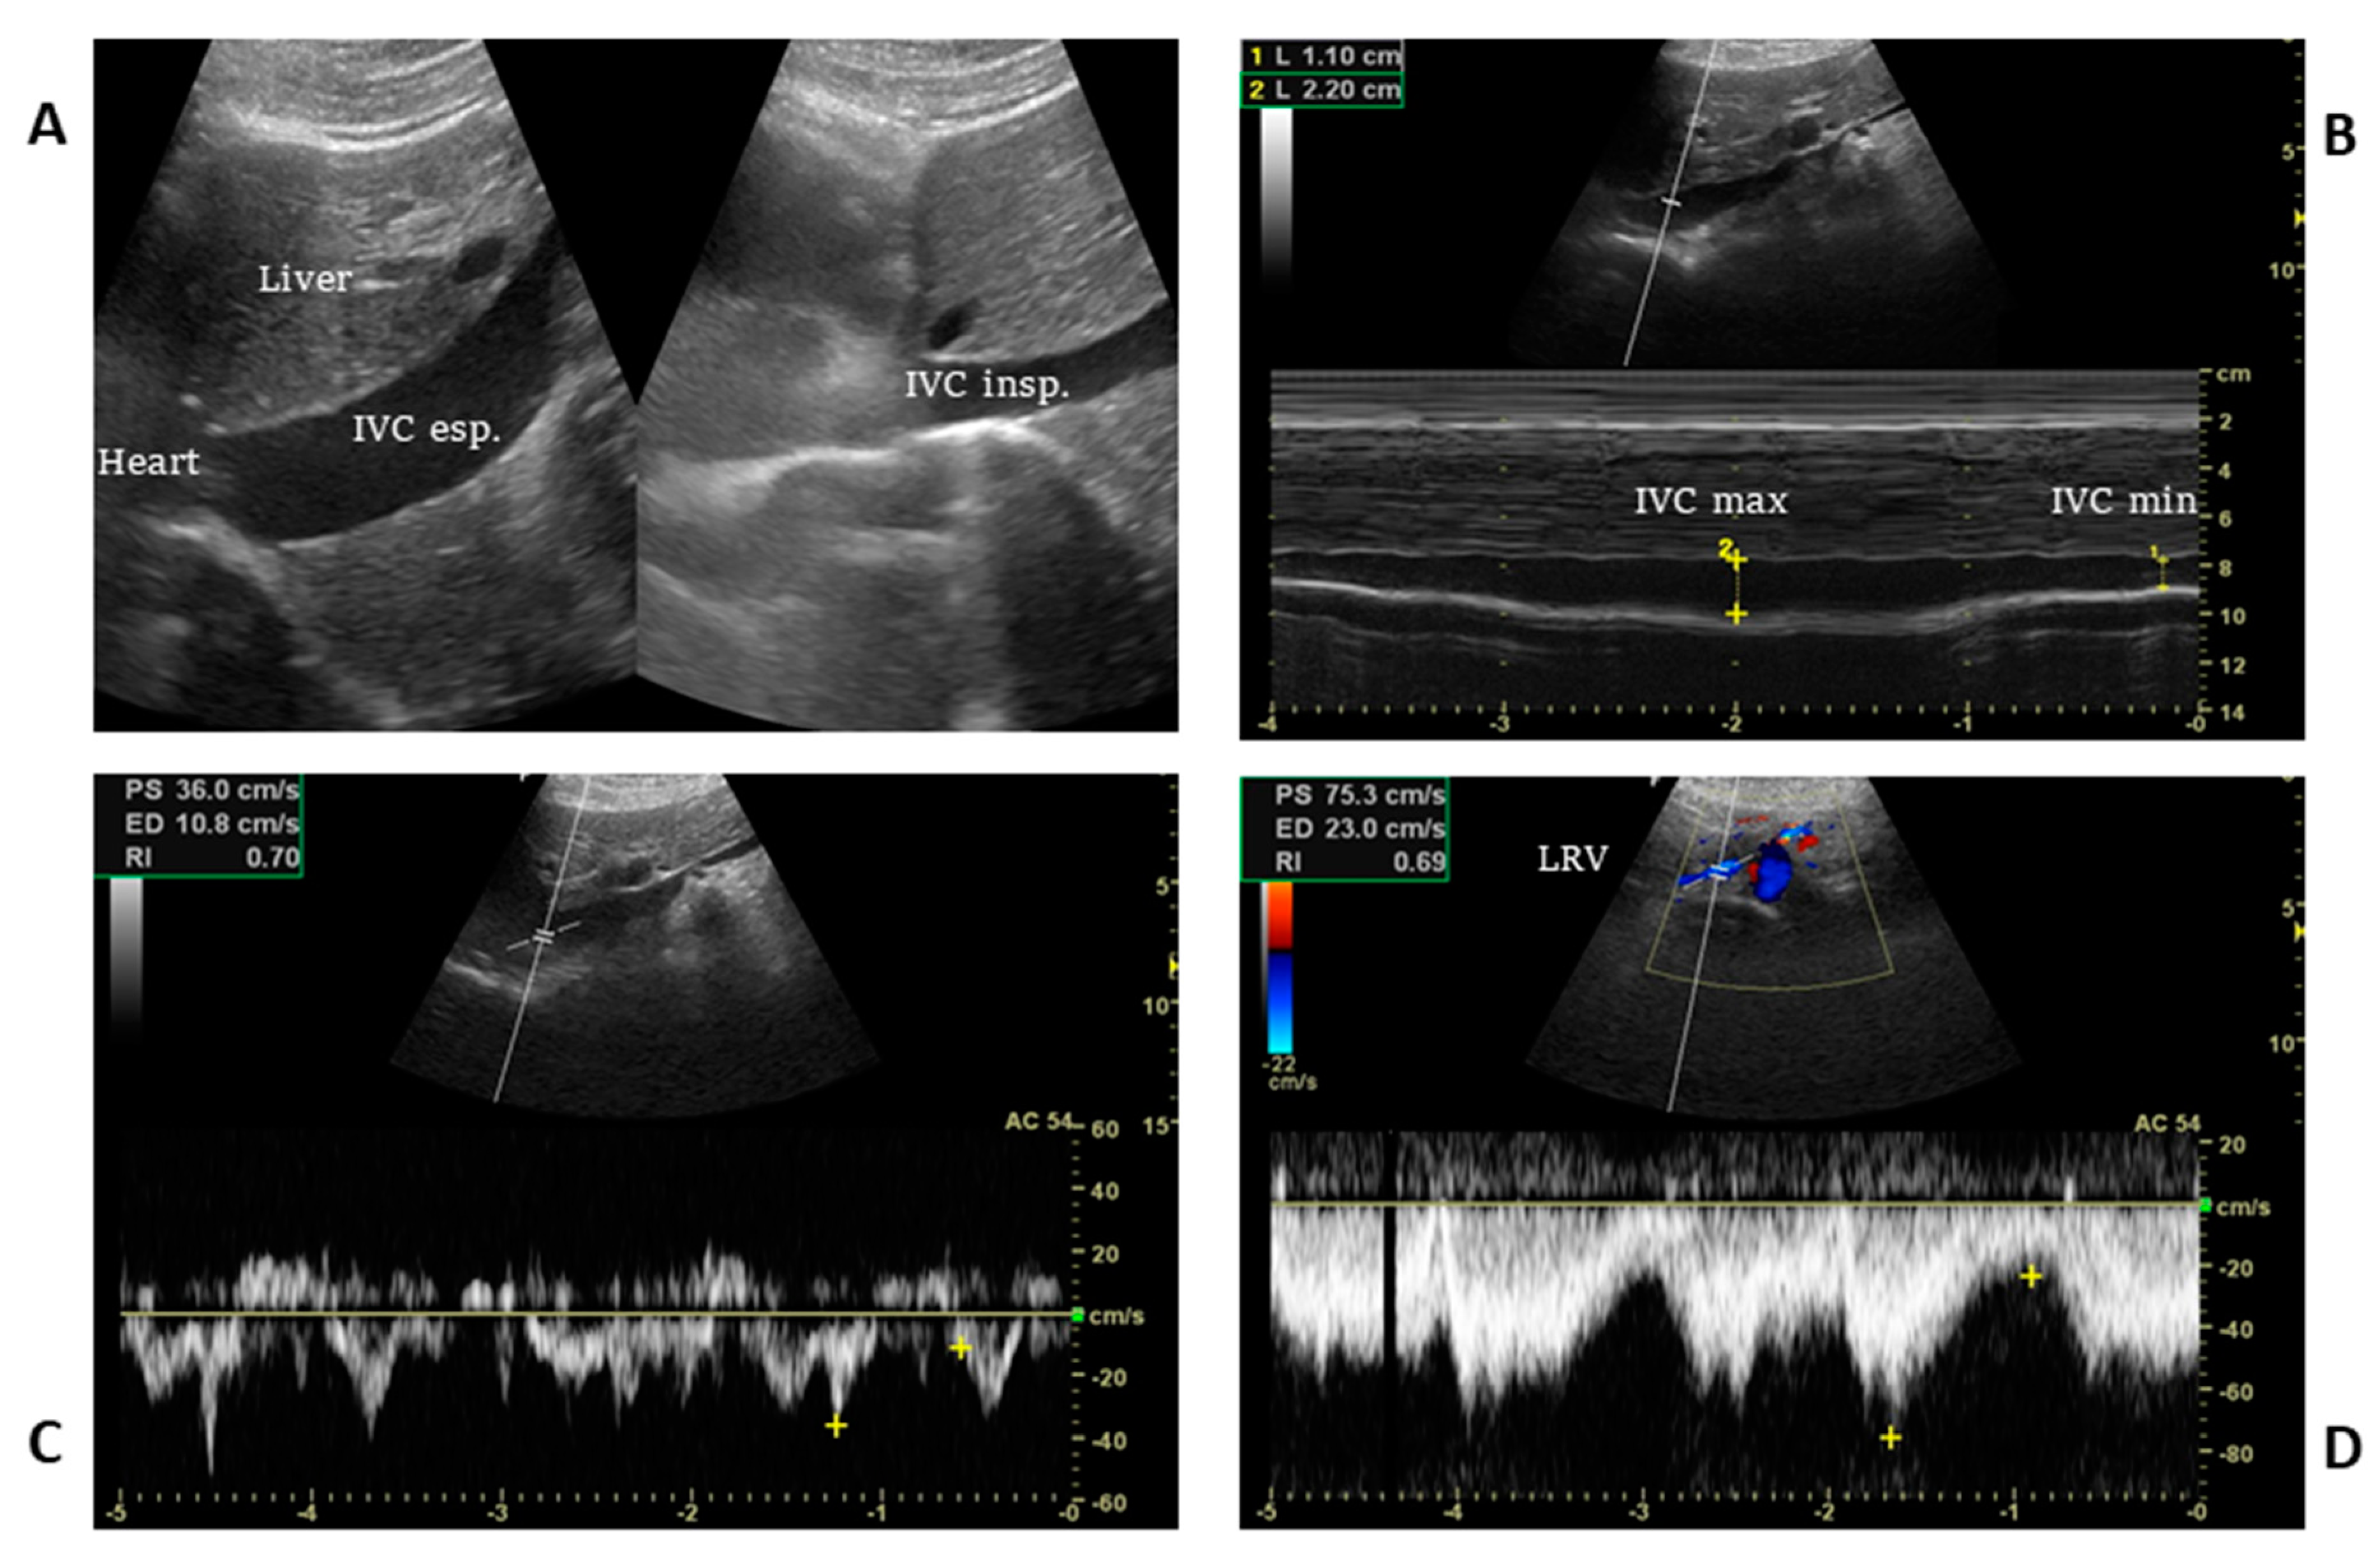

4. Ultrasound Technique, Static and Dynamic IVC Indexes